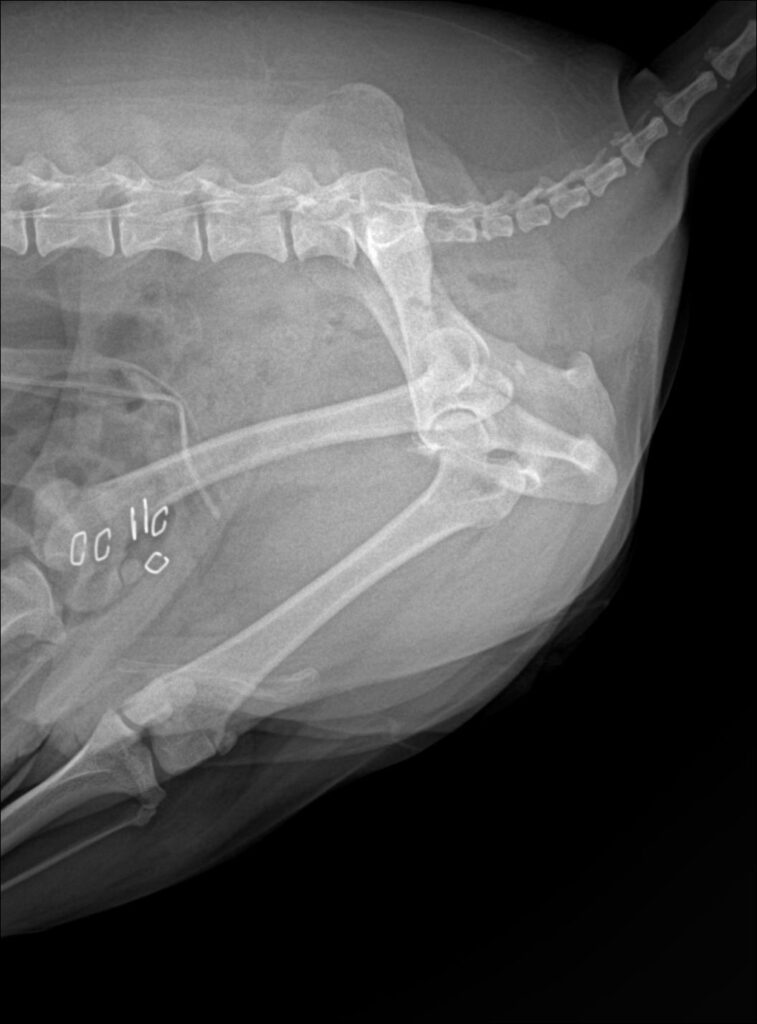

수술 직후에는 엑스레이 촬영을 통해 잔존 결석이 남아 있지 않은 것을 확인했습니다.

수술 후 방사선 검사 / 출처: 미래동물의료센터